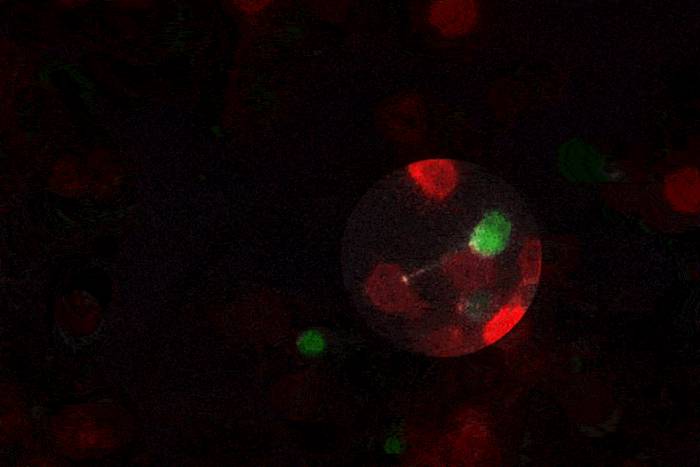

Researchers successfully modified immune cells to produce antibodies that fight HIV. This strategy could eventually be used to develop a vaccine against the virus, among other conditions.